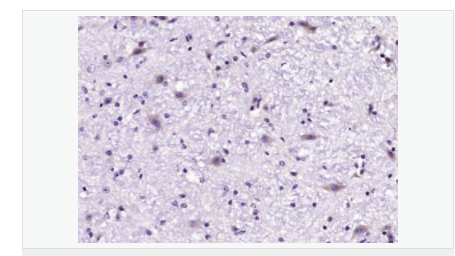

產(chǎn)品介紹GLRB (Glycine receptor beta) is a neurotransmitter-gated ion channel concentrated within the spinal cord and brainstem. Expression is also observed in several upper brain regions including the cortex, cerebellum, hippocampus and amygdala. Binding of glycine to GLRB increases the chloride conductance and thus produces hyperpolarization (inhibition of neuronal firing), controlling spinal reflexes and locomotor behavior.

image.png